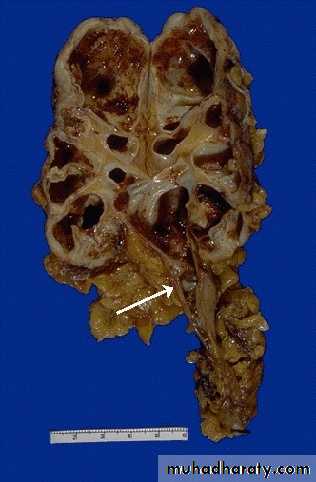

Grossly, the lesion produces large, yellowish/orange mass that may be confused with renal cell carcinomaHydronephrosis: dilatation of renal pelvis and calyces associated with progressive atrophy of the renal parenchyma due to obstruction of urine out flow.